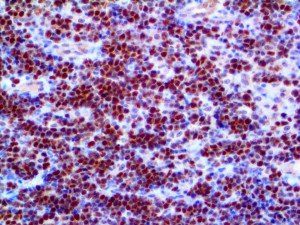

It is the ICU physician who is most likely to witness one of the deadliest manifestations of the abnormal immunological response, the cytokine storm syndrome (CSS). This response is also referred to by some as the cytokine release syndrome (CRS). CSS is characterized by continuous activation and expansion of macrophage and lymphocyte populations, which secrete large amounts of cytokines, causing the cytokine storm. This massive cytokine release is akin to hemophagocytic lymphohistiocytosis (HLH) disease, a syndrome characterized by initial unchecked and persistent activation of cytotoxic T lymphocytes and NK cells.

Clinical and laboratory manifestations of HLH include fever, enlarged liver and/or spleen, neurologic dysfunction, coagulopathy, liver dysfunction, cytopenias (i.e., low levels of erythrocytes, leukocytes, and/or platelets), hypertriglyceridemia, hyperferritinemia, hemophagocytosis, and eventually diminished NK cell activity as the immune system becomes progressively paralyzed. HLH can be familial (primary HLH) or secondary to another disease process (sHLH), such as rheumatic disease, in which it is referred to as macrophage activation syndrome (MAS, characterized by elevated ferritin).